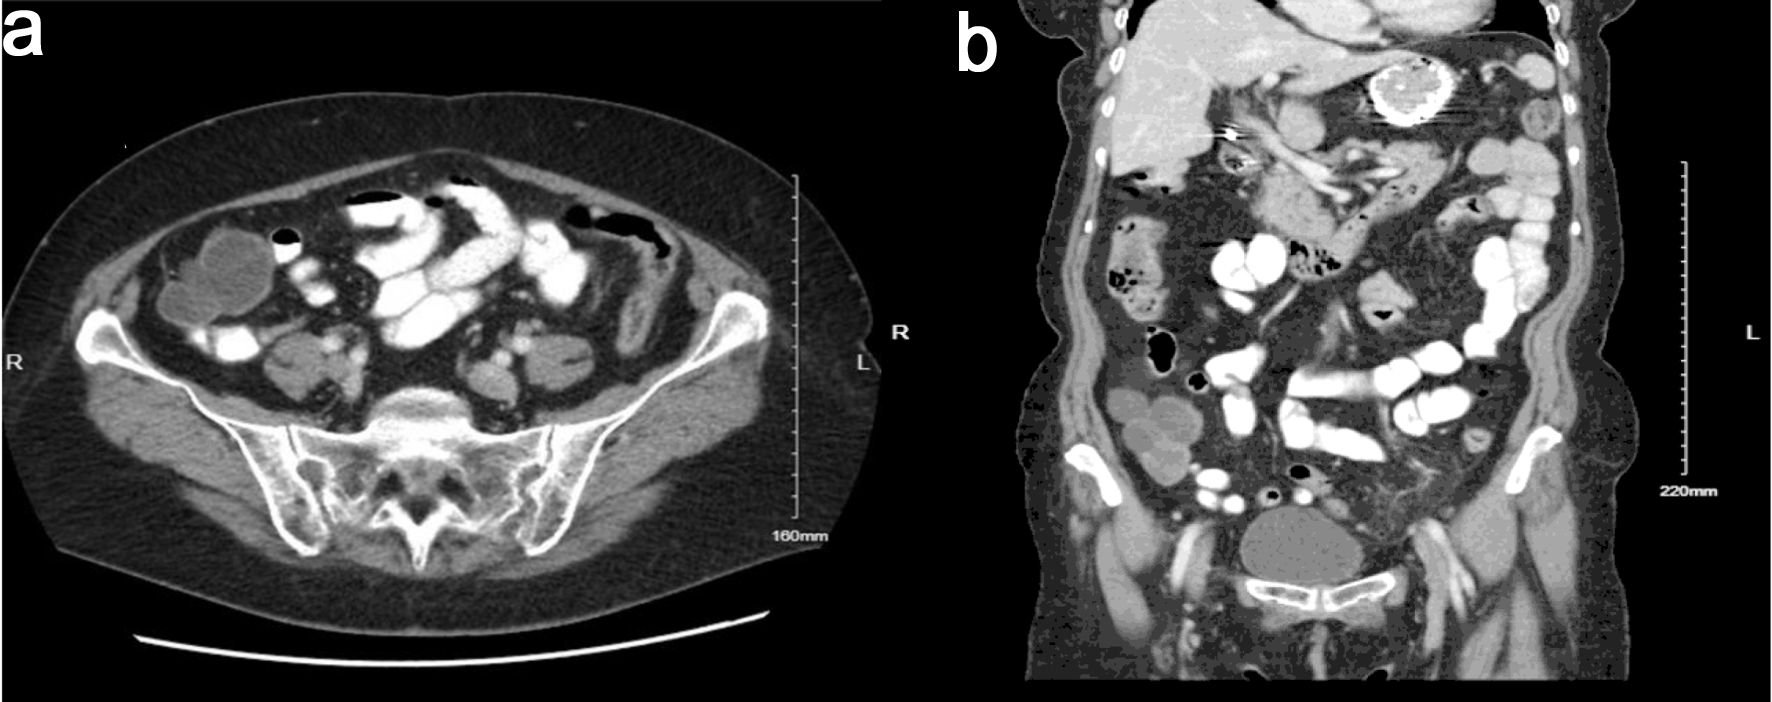

In March 2020, she initially underwent a pelvic ultrasound that showed a 5.3 × 5.3 × 4.7 cm multiseptated cystic lesion on the right ovary and a 2.8 × 2.1 × 2.8 cm septated cyst on the left ovary. MRI of pelvis as well as further gynecologic evaluation were recommended. In April 2021, she presented to an adjacent hospital system where she was evaluated in the emergency room for lower abdominal pain. A computed tomography (CT) scan of the abdomen and pelvis was performed. The CT scan showed a 5.0 × 3.6 × 4.3 cm low-density nodule posterior and rightward of the uterus, associated with the right ovary and a 3.0 × 4.2 × 3.0 cm low-density nodule anterior and leftward of the uterus, associated with the left ovary. Additionally, there was a 9 mm enhancing nodule in the posterior cecal wall, not previously seen on initial imaging, as well as a multi-lobulated multicystic complex mass anterior to the inferior cecum. As a result, she was later sent for a pelvic MRI which still showed bilateral ovarian pathology seen on previous imaging. The MRI (Fig. 1, key image) showed complex multicystic changes in the right ovary measuring 3.4 × 3.3 × 3.4 cm with multiple thin septations. The left adnexa showed similar complex multicystic changes (3.6 × 1.8 × 2.1 cm with multiple thin septations). The multicystic omental mass was still visualized along the medial aspect of the cecum measuring approximately 6.2 × 4.0 × 3.6 cm with a dominant septation traversing the mass. The cystic lesion did not seem to originate from sigmoid or uterus. She then underwent a colonoscopy which did not show any intrinsic rectal or sigmoid disease.

Figure 1. Coronal MRI images demonstrate an omental cystadenofibroma and an ovarian cystadenofibroma. The omental lesion appears as a well-circumscribed cystic mass within the anterior abdominal cavity, consistent with a benign omental implant, while the ovarian cystadenofibroma is located lower in the pelvis adjacent to the uterus, showing mixed cystic and solid components typical of epithelial origin. MRI: magnetic resonance imaging.